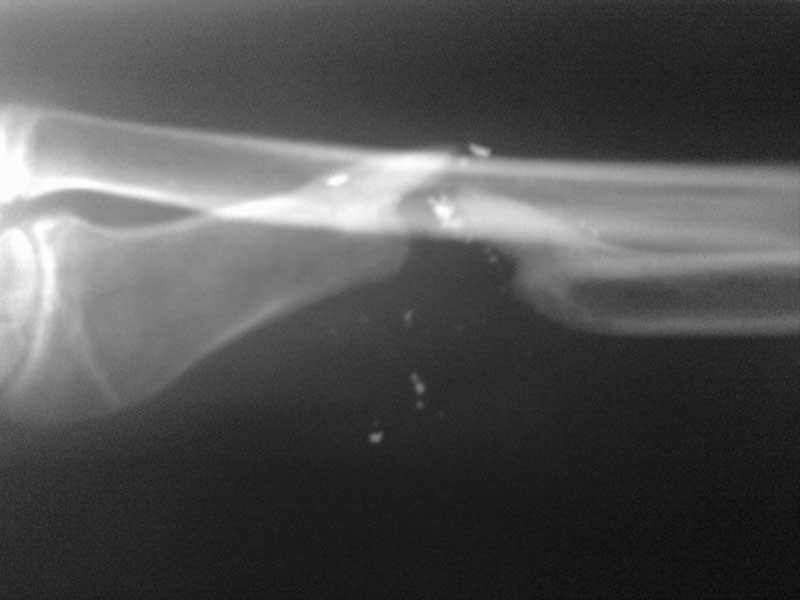

Дефект лучевой кости

Больной 16 лет, в июле 2011 получил в результате неосторожного обращения с огнестрельным оружием, дробовое огнестрельное ранение левого предплечья.

Первая помощь оказана в условиях ЦРБ, раны зажили, кожа чистая, рубцы состоятельны. Ангионевротических расстройств нет. Интересует мнение коллег по тактике лечения в плане замещения костного дефекта. Cпасибо заранее.

При дефекте лучевой кости до 5-6 см, можно выполнить его замещение свободным костным аутотрансплантатом из гребня подвздошной кости с фиксацией пластиной с угловой стабильностью винтов. При дефекте большей длины, целесообразно выполнить замещение дефекта кровоснабжаемым фрагментом малоберцовой кости в составе свободного кожно-костного комплекса тканей с фиксацией костного трансплантата проведенной по оси лучевой кости спицей Киршнера. Фрагменты лучевой кости фиксировать в аппарате внешней фиксации. Последний вариант операции возможен при сохраненном кровотоке по локтевой артерии и сохранившейся проксимальной части лучевой, что необходимо выяснить при контрастном способе обследования (ангиография, КТ, МРТ).